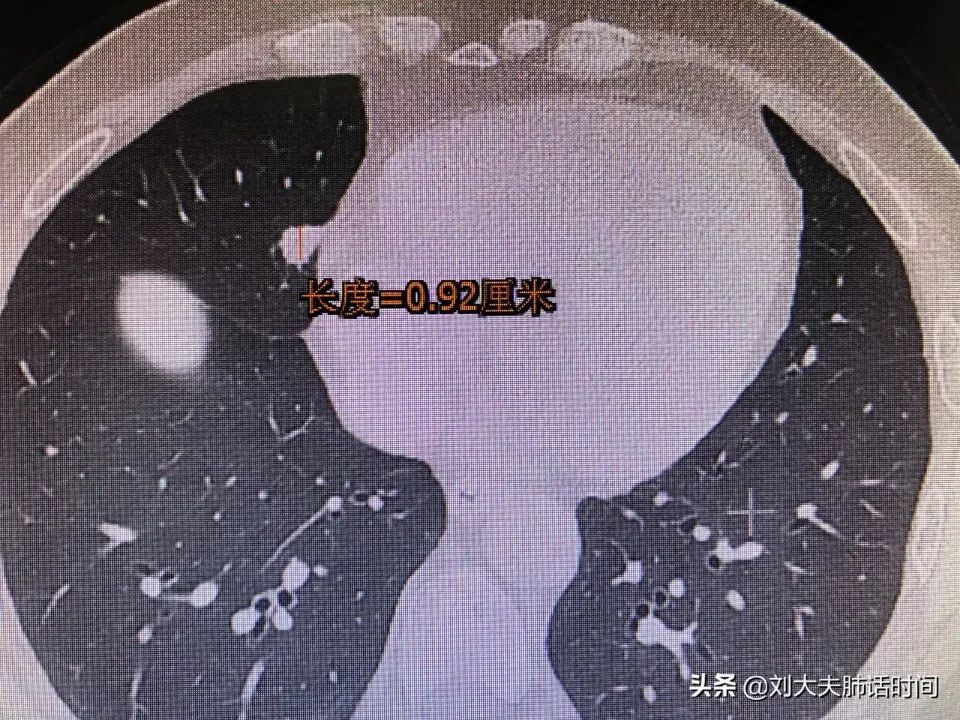

就比如下面两张报告

(报告1良性,报告2恶性)

肺结节中,95%都是良性结节,不需要做手术,只有5%是恶性结节(肺癌)。

判断肺结节是良性还是恶性,先随访3个月比较肺结节的外部结构和内部特征非常重要。